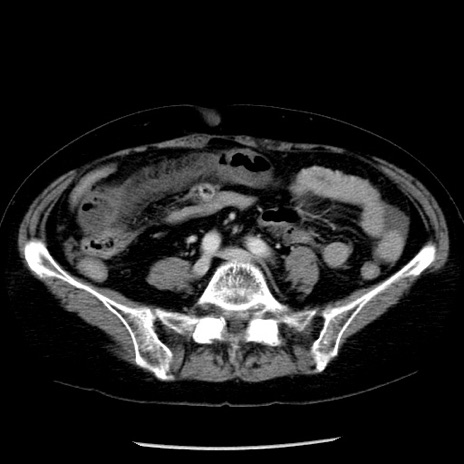

症例13(横断像)

【症例】70歳代女性

【主訴】腹痛、嘔吐

【現病歴】15時間程前(昨晩)より腹痛あり。今朝になっても症状の改善なく、嘔吐あり。腹痛も増悪あり、救急外来受診。

【既往歴】子宮癌全摘術後

【身体所見】意識清明、BP 121/72mmHg、P 74bpm、SpO2 100%(RA)、腹部:平坦・軟、腸雑音ほぼ聴取せず。下腹部・心窩部・臍左上に圧痛あり。反跳痛なし。

【データ】WBC 10600、CRP 0.15